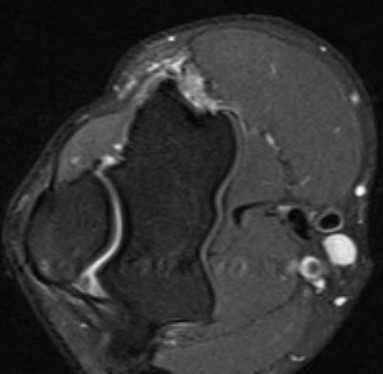

а) МРТ локтевого сустава в аксиальной плоскости

б)МРТ локтевого сустава в корональной плоскости. Общее сухожилие разгибателей в месте прикрепления к латеральному надмыщелку плечевой кости неравномерно утолщено, МР-сигнал от него неоднородно повышен на PD FS-ВИ и Т2-ВИ за счет выраженного отека и разволокнения (признаки латерального эпикондилита), общая целость его не нарушена. Окружающие мягкие ткани с признаками отека.